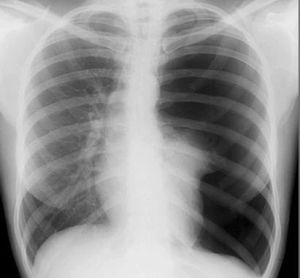

1.影像學檢查

X線檢查是診斷氣胸的重要方法。胸片作為氣胸診斷的常規手段,若臨床高度懷疑氣胸而後前位胸片正常時,應該進行側位胸片或者側臥位胸片檢查。氣胸胸片上大多有明確的氣胸線,為萎縮肺組織與胸膜腔內氣體交界線,呈外凸線條影,氣胸線外為無肺紋理的透光區,線內為壓縮的肺組織。大量氣胸時可見縱隔、心臟向健側移位。合併胸腔積液時可見氣液面。局限性氣胸在後前位X線檢查時易漏診,側位胸片可協助診斷,X線透視下轉動體位也可發現。若圍繞心緣旁有透光帶應考慮有縱隔氣腫。胸片是最常套用於診斷氣胸的檢查方法,CT對於小量氣胸、局限性氣胸以及肺大皰與氣胸的鑑別比X線胸片敏感和準確。氣胸的基本CT表現為胸膜腔內出現極低密度的氣體影,伴有肺組織不同程度的壓縮萎陷改變。

2.氣胸的容量

就容積而言,很難從X線胸片精確估計。如果需要精確估計氣胸的容量,CT掃描是最好的方法。另外,CT掃描還是氣胸與某些疑難病例(例如肺壓縮不明顯而出現窒息的外科性肺氣腫、複雜性囊性肺疾病有可疑性肺大皰等)相鑑別的惟一有效手段。

根據臨床症狀、體徵及X線表現,診斷本病並不困難。阻塞性肺氣腫並發自發性氣胸時,與其原有的症狀和體徵常易混淆,需藉助X線檢查作出診斷。